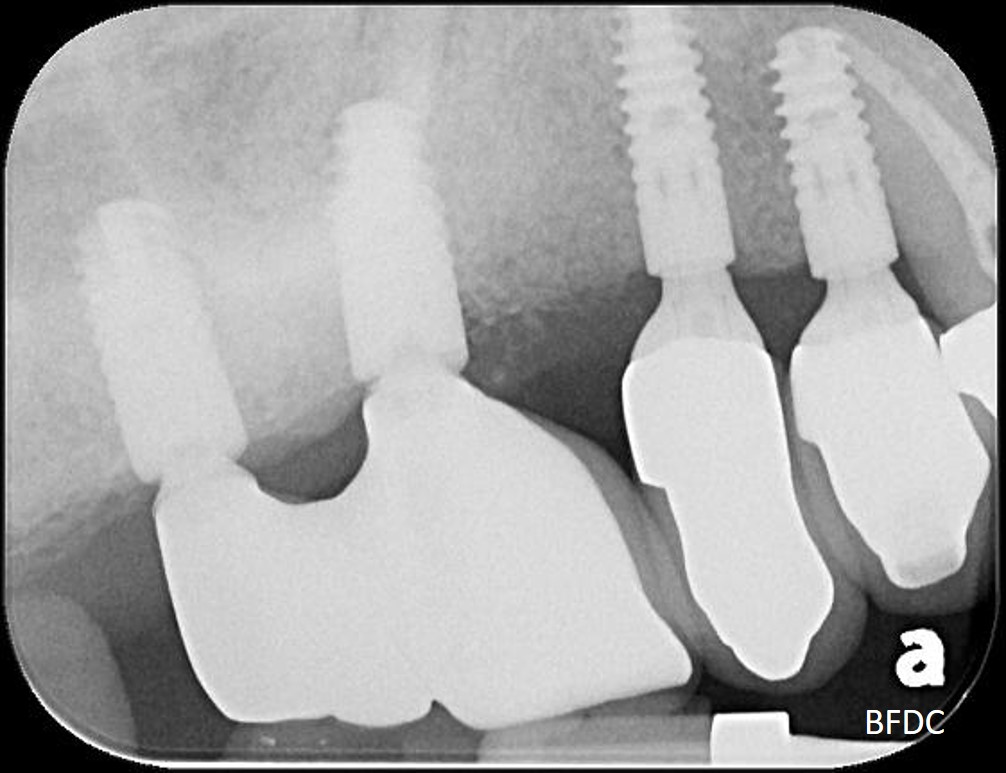

5年前,植牙剛完成

5年前,植牙剛完成,術後X光,骨癒合良好

5年後追蹤,植體周圍骨破壞

植體清創、並施予骨粉